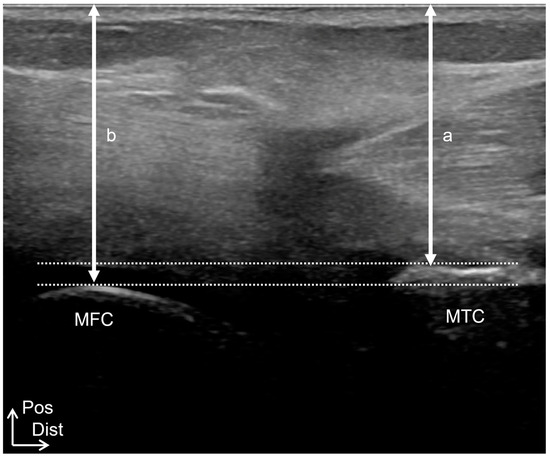

Relationship Between the Sagittal and Coronary Alignment of the Tibiofemoral Joint and the Medial Meniscus Extrusion in Knee Osteoarthritis

Background/Objectives: This study aims to clarify the reproducibility, validity, and accuracy of tibial external-rotation alignment evaluation using ultrasound imaging and to investigate the relationship between medial meniscus extrusion (MME) and tibiofemoral alignment in both the sagittal and coronal planes in knee osteoarthritis [...] Read more.

Background/Objectives: This study aims to clarify the reproducibility, validity, and accuracy of tibial external-rotation alignment evaluation using ultrasound imaging and to investigate the relationship between medial meniscus extrusion (MME) and tibiofemoral alignment in both the sagittal and coronal planes in knee osteoarthritis (OA). Methods: Study 1 included 10 healthy participants. The tibial external-rotation angle was calculated using MRI. In the ultrasound imaging evaluation, the differences in the distance from the most posterior points of the tibial and femoral condyles to the skin were calculated as the medial and lateral condyle gaps, respectively. The mediolateral (ML) gap was calculated by subtracting the lateral condyle gap from the medial condyle gap. Study 2 included 63 patients with unilateral OA and 16 healthy controls. MME was compared according to the severity of OA, the degree of tibial rotation, and the presence or absence of a tibial posterior shift. Results: Ultrasound imaging examinations showed high intra- and inter-rater reliabilities (0.786–0.979). The ML gap significantly affected the tibial external-rotation angle, determined using MRI. The ML gap of ultrasound imaging was significantly correlated with the ML gap of MRI. MME was significantly higher in the Early OA group than in the Control group. There was no significant difference in MME based on the tibial rotation degree. The group with a tibial posterior shift exhibited significantly more MME than that without a posterior shift. Conclusions: Ultrasound imaging is useful for evaluating knee alignment. MME was found to be associated with the tibial posterior shift. Full article